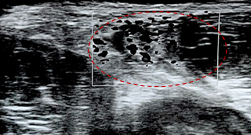

This clinical case concerns a 25-year-old healthy young man, a semi-professional football player who developed pain in the anterior thigh and right inguinal region after a hip hyperextension movement under load during a football game. Following the event, he presented a limp, with his trunk in anterior flexion, as he could not tolerate the neutral position. He experienced pain during resisted hip flexion and in the knee flexion/extension movements. At the time of the event, he reported moderate to intense pain using the numeric rate scale (NRS 7/10). After 36 hours, he underwent a musculoskeletal ultrasonography (US) that showed signal alteration at the myotendinous junction of the sartorius and rectus femoris muscles, highlighted in Figure 1 by a dashed red circle, consistent with a probable myotendinous rupture of the rectus femoris, as well as the presence of a hematoma, indicated in Figure 2 by the red arrows. At the time of the US, there was a slight improvement in pain (NRS 5/10). After 72 hours from the incident, a bruise developed on the anterior thigh, as illustrated in Figure 3.

He underwent pharmacological treatment with paracetamol 1000mg every 12 hours, along with physiotherapy treatments, which included ultrasound, draining massage, compression, and dynamic ice therapy. He also received one session of moist heat, but this exacerbated the bruise, leading to the suspension of further treatment. Two weeks after the injury, he underwent a Magnetic ressonance imaging (MRI) of the thigh, which showed an extensive proximal rupture of the right rectus femoris muscle, with a hematoma measuring approximately 61 * 36 * 19, as outlined by the dashed yellow circle in Figure 4. He did not undergo a period of rest and started quadriceps strengthening exercises 3 weeks after the injury due to the absence of pain while walking. Currently, in the 4th week after the event, he is pain-free while walking, with no limitations or pain in active hip and knee movements. He is tolerating concentric and eccentric quadriceps exercises using only body weight, experiencing pain only during the passive stretching of the quadriceps.

Injuries to the proximal rectus femoris tendon often occur due to kicking motions.1 During the backswing of a kick, when the hip is hyperextended and the knee is flexed, the rectus femoris is under significant tension. The final phase of the backswing involves a powerful eccentric contraction, which places the RF tendon at a high risk of injury.6 Several risk factors have been identified for quadriceps muscle injuries, which can be categorized into intrinsic (age, previous injury, short height and high body weight, leg dominance, flexibility, strength) and extrinsic factors (dry field).6 The key factors that may offer the best chance to prevent rectus femoris injuries are flexibility, strength, and core stability.6 The diagnosis of rectus femoris tendon injuries is usually made clinically, based on the injury mechanism and physical examination. US is an effective point-of-care diagnostic tool, particularly in cases involving edema or hematoma, and can help monitor the recovery of rectus femoris injuries.7 MRI is the gold standard imaging technique for confirming the diagnosis and detailing the characteristics of the tendon injury,8 as demonstrated in the presented case. The MRI grading of myotendinous injuries is classified from I to III. Grade I tears are characterized by a high-intensity signal at an intact myotendinous junction. Grade II tears involve partial disruption of the myotendinous junction. Grade III tears represent a complete myotendinous disruption, with or without retraction. A more recent grading system proposed by British Athletics offers a detailed classification based on both the extent (grades 0 to 4) and the location of the injury (a – myofascial, b - muscular/musculotendinous, c - intratendinous).1